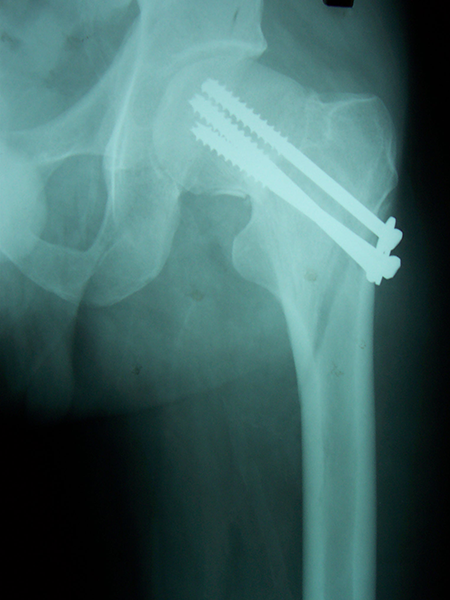

Case:1 Polytrauma Case (Multiple Fractures in Ipsilateral Limb)

Pre-Op Hip (AP & Lateral)

Post-Op Hip

4 Months Post Operative X-ray showing #s united

3 Months Follow up